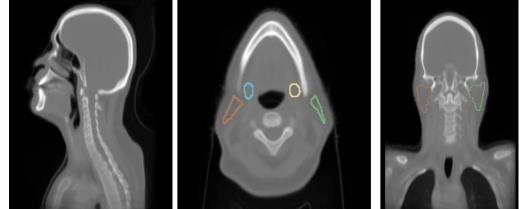

Deep learning xerostomia prediction model with anatomy normalization and high-resolution class activation map

We develop an interpretable deep learning model for xerostomia prediction using anatomy normalization and high-resolution class activation maps for improved spatial interpretability.

Bohua Wan, T. McNutt, H. Quon, J. Lee

Proc. SPIE Medical Imaging 2025 (2025).